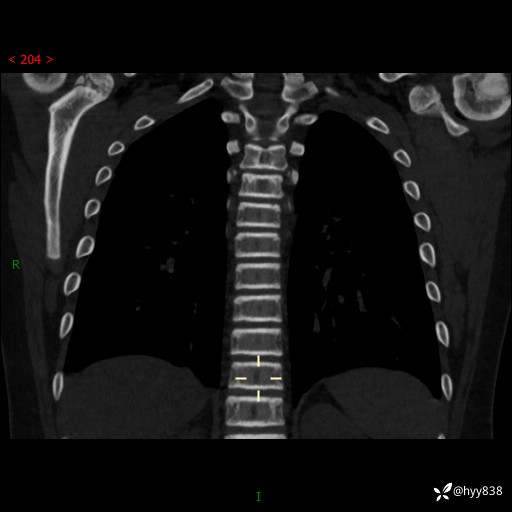

胸部CT脊柱MPR

img

2015年胸片